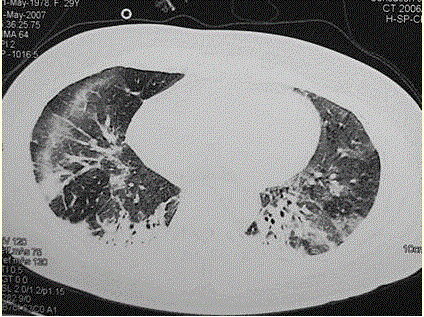

问题 患者女,29岁。间断干咳10年余,加重4个月,伴进行性呼吸困难1个月。病程中出现双手及双足非凹陷性肿胀、双侧膝关节及双侧肘关节对称性肿痛,面部出现细小红色丘疹。体检:T 36.5℃,P 88次/min,R 22次/min,BP 110/75 mmHg,SpO 93%(自然)。额部、前胸及后背散在红色小丘疹,双肺呼吸音增强,双肺中下肺野可闻及爆裂音,右肺明显。胸部CT 如图所示。 该患者最可能的诊断是(提示 患者无发

选项 A.肺泡蛋白沉积症 B.军团菌肺炎 C.特发性间质性肺炎 D.结缔组织病肺受累 E.肺部恶性肿瘤 F.结节病 G.社区获得性肺炎

答案 D